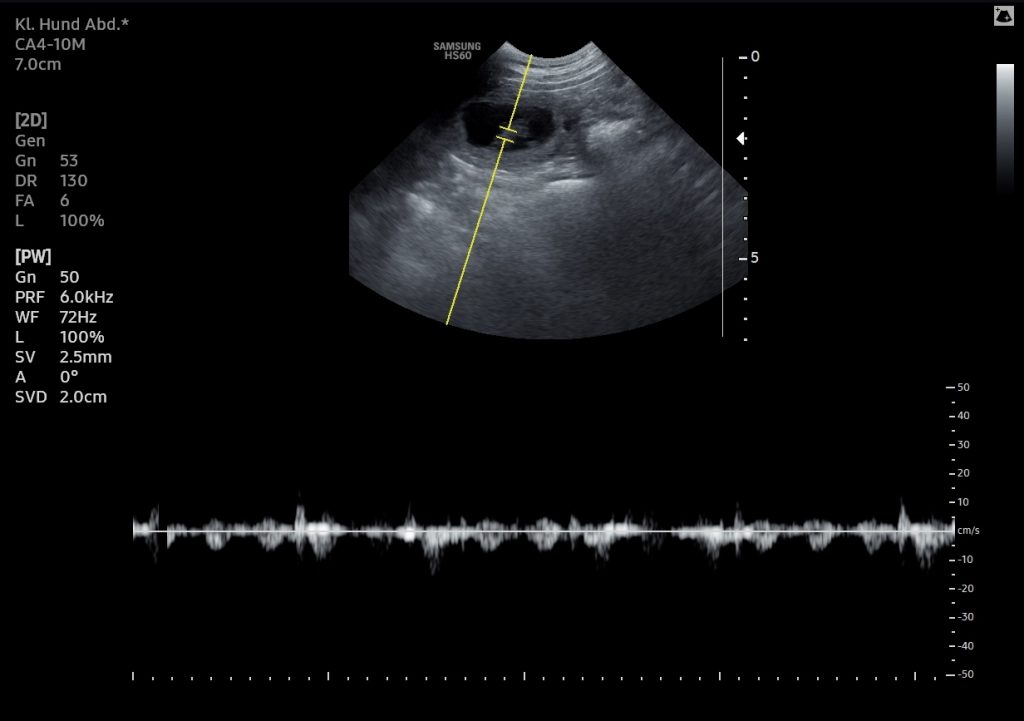

Der Ultraschall hat es bestätigt: Hedda vom Landgöding ist tragend – es sind mindestens 6 Fruchtanlagen zu erkennen. Juhu!

Die kleinen Herzen schlagen bereits und wir freuen uns sehr auf das, was nun vor uns liegt.